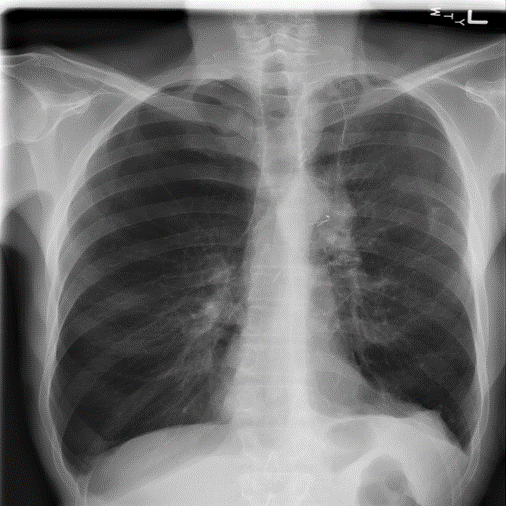

Figure 9: Typical CXRs with pneumonia-like lung opacity from among the top 1,000 CXRs most likely to have an abnormality according to the logarithm posterior probability out of the 13,863 abnormal CXRs. The lesion is indicated with a red arrow if applicable.

Figure 9 shows CXRs suggested to have pneumonia-like lung opacity with the logarithm posterior probability. These CXRs are the top 1,000 CXRs most likely to have an abnormality out of the 13,863 abnormal CXRs.